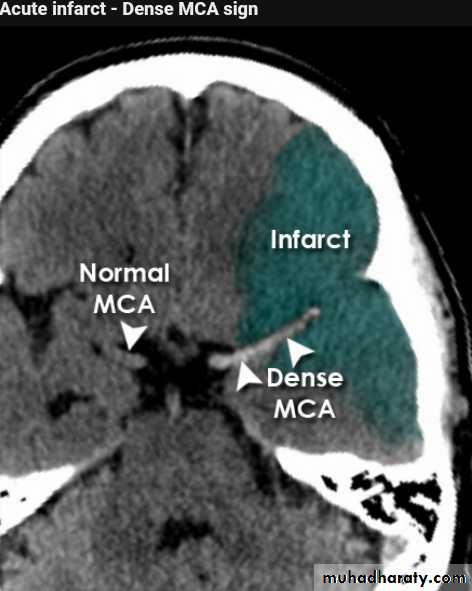

Acute infarction

History: sudden onset of hemiplegia , with slurred speech .

CT features:

Wedge shape area of hypo density involve the tributaries of anterior , middle or posterior cerebral arteries , ( i.e. priato frontal &priato occipital area )

Shift of the midline to the other side .

Compression of the ipsi lateral aspect of the regional ventricle by the edema

Dense middle artery sign

* wedge shape hypo density area.* Shifting of the midline & frontal horn